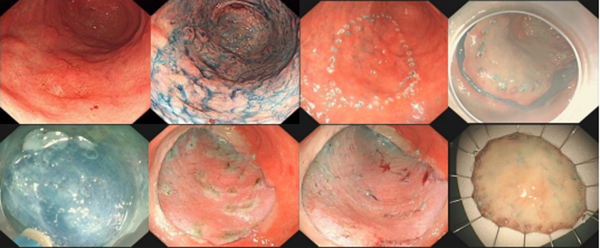

消化道早癌与大众认知的癌不同的是,诊断为消化道早癌意味着病变发现的很及时,换句话说,此时若获得准确诊断及规范化治疗,是可以获得治愈效果的,且不管是食管、胃还是结直肠的黏膜内癌或高级别上皮内瘤变,都可以通过不开刀的内镜下微创治疗取得治愈效果。以早期胃癌为例,可以通过内镜黏膜下剥离术(ESD)将病变从内镜下完整切除。内镜黏膜下剥离术(ESD)操作过程如下图所示,内镜医师使用刀头长度仅2mm的内镜专用刀,将病变及周围黏膜所在的黏膜层及黏膜下层剥离下来,使病变获得整块切除。内镜下治疗后的手术标本需再次送检病理科,制作成病理切片,以供病理科医师出具最终的病理报告。若最终病理报告提示病变已经完整切除,那么后续仅需要定期复查胃肠镜即可,不需要追加外科手术或放化疗。